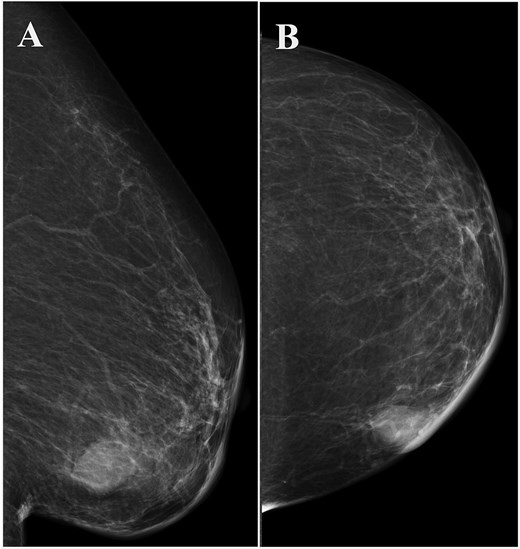

Left breast mammography showing a focal asymmetric density of ~1 cm in diameter in the inner-lower region. (A) Medio-lateral oblique view, (B) cranio-caudal view.

A 93-year-old woman presented to the outpatient breast clinic with a 2-day history of pain and redness in the left breast. She reported that she had not noticed a nodule in left breast previously. Physical examination revealed a soft-to-hard nodule of ~1 cm in diameter in the inner lower region of the left breast, accompanied by redness, blistering, and soreness of the surrounding skin (Fig. 1). Her body temperature was 36.5°C, and laboratory data and vital signs were unremarkable. Mammography revealed a focal asymmetric density of ~1 cm in diameter in the inner lower region of the left breast (Fig. 2A and B), and B-mode ultrasound imaging indicated that the nodule was mainly located in the subcutaneous fat layer along with dorsal acoustic amplification and lateral shadowing, and was characterized by a heterogeneous pattern with a hypoechoic rim that was ill-defined on the nipple side (Fig. 3A). In addition, color Doppler sonography showed blood flow signals primarily near the nodule (Fig. 3B), whereas the nodule appeared green-to-orange on ultrasound elastography (Fig. 3C). We used an ultrasound-guided VABD (Mammotome ® Elite ™) for pathological examination and to reduce inflammation. After local anesthesia, a 5-mm skin incision was made away from the inflamed skin on the nipple side of the lesion. Under ultrasound guidance, a 10-gauge operating needle was advanced through the incision (Fig. 4A) and positioned posterior to the lesion (Fig. 4B). The direction of the needle head aperture was adjusted to face the lesion in multiple directions. The lesion was excised toward the skin using a rotating blade with vacuum aspiration (Fig. 4C), and this maneuver was repeated without significantly affecting the overlying skin. The time from insertion to removal of operating needle was 5 min, and the obtained specimens were sent for bacterial culture and pathological examination. Upon completion of the procedure, a compression dressing with gauze was applied for 1 day. No further wound healing care was provided. Histological examination revealed that the lesion comprised mature stratified squamous epithelium and laminated layers of keratin, which was consistent with an EC (Fig. 4D). Examination of bacterial cultures at 9 days after the treatment revealed the presence of Prevotella bivia, Peptostreptococcus asaccharolytics, and Staphylococcus epidermidis. However, the inflammation had subsided before the bacterial examination report was obtained. Although the symptoms and inflammation disappeared within a week post-treatment, a red nodule of 4–5 mm in diameter persisted (Fig. 5A). Ultrasound images